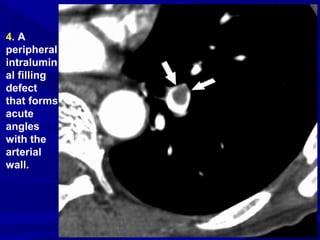

4. A

peripheral

intralumin

al filling

defect

that forms

acute

angles

with the

arterial

wall.